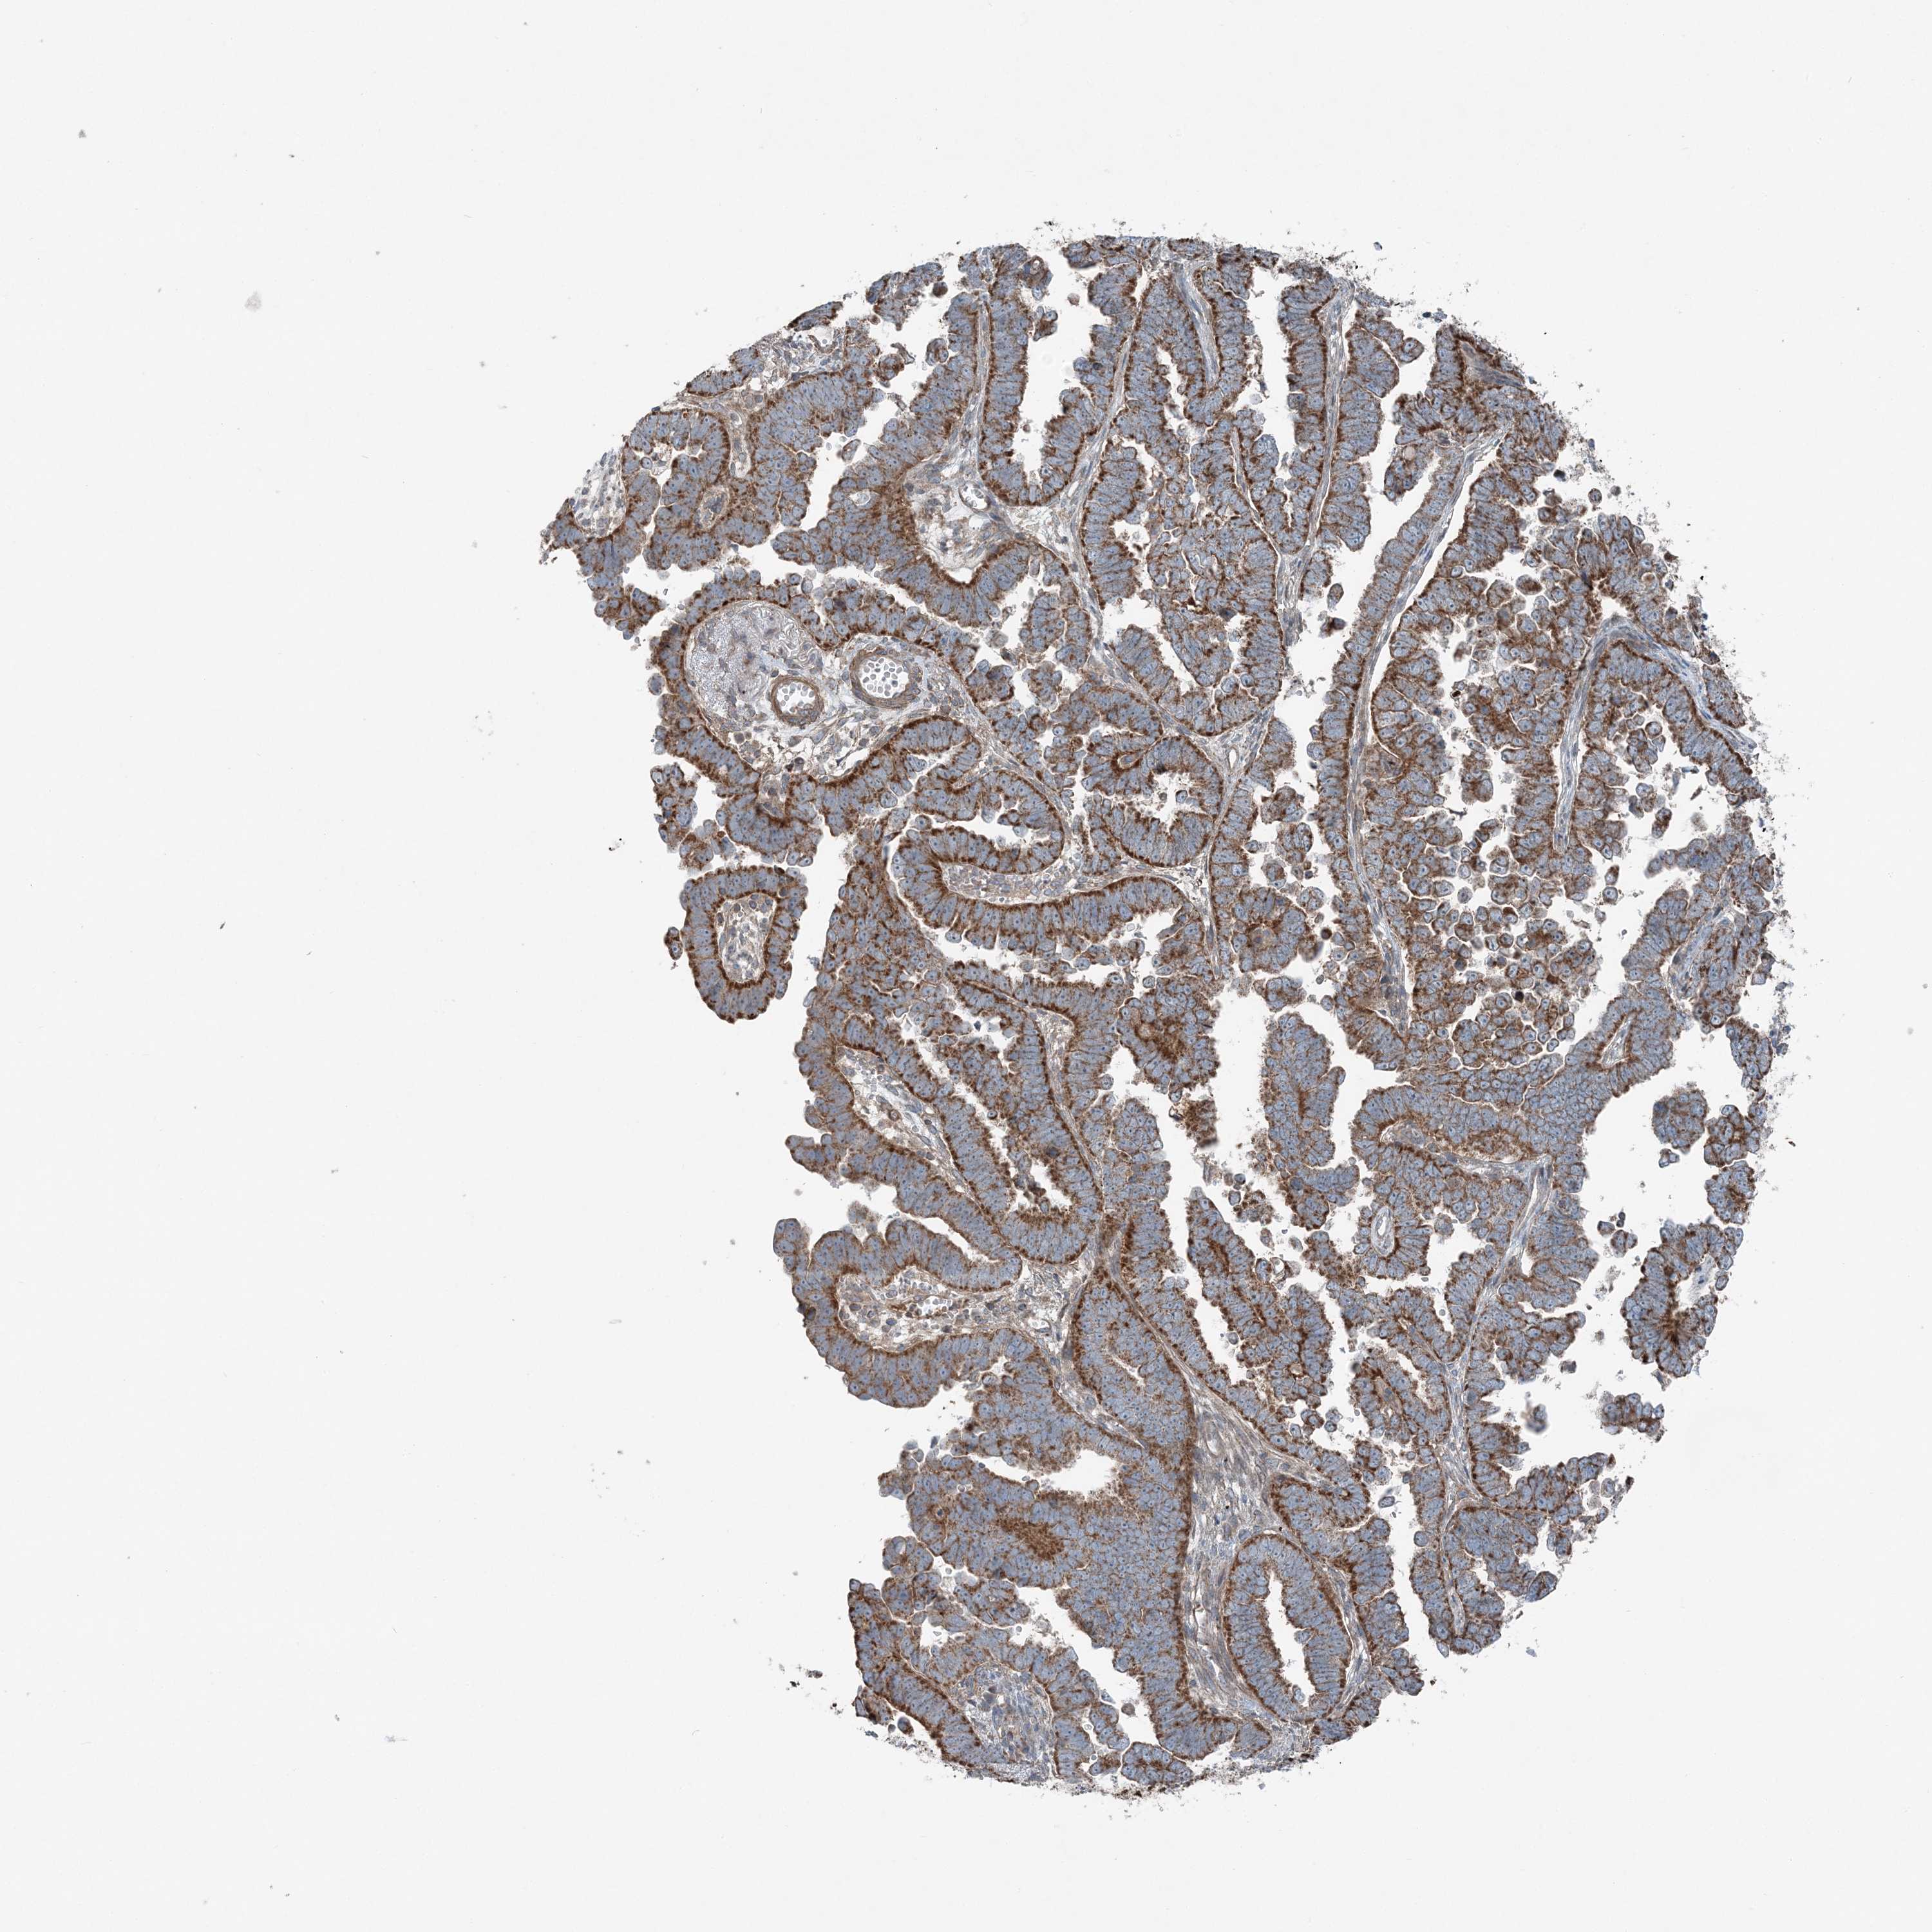

ENDOMETRIAL CANCER - Protein expressioni

A mouse-over function shows sample information and annotation data. Click on an image to view it in a full screen mode. Samples can be filtered based on level of antibody staining by selecting one or several of the following categories: high, medium, low and not detected. The assay and annotation is described here.

Note that samples used for immunohistochemistry by the Human Protein Atlas do not correspond to samples in the TCGA dataset.

Antibody stainingi

Antibody staining in the annotated cell types in the current human tissue is reported as not detected, low, medium, or high, based on conventional immunohistochemistry profiling in selected tissues. This score is based on the combination of the staining intensity and fraction of stained cells.

Each image is clickable and will lead to virtual microscopy that enables deeper exploration of all samples and also displays staining intensity scores, fraction scores and subcellular localization as well as patient and tissue information for each sample.

Antibody HPA036492

Antibody HPA036668

Staining

High

Medium

Low

Not detected

Intensity

Strong

Moderate

Weak

Negative

Quantity

>75%

75%-25%

<25%

None

Location

Nuclear

Cytoplasmic/membranous

Cytoplasmic/membranous,nuclear

Adenocarcinoma, NOS